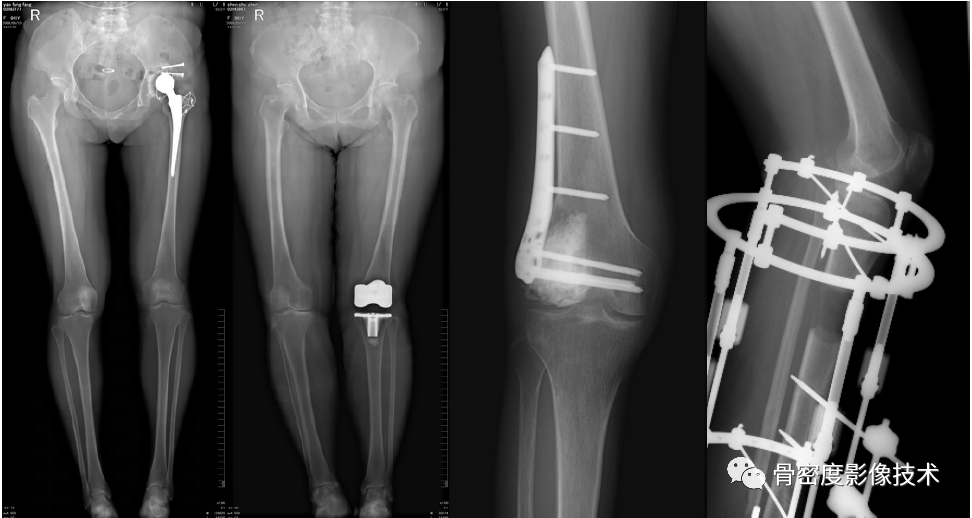

应用适应症:全下肢摄影—人工髋关节、膝关节置换以及下肢不等长畸形的矫正和O、X型腿畸形的矫正。可进行骨密度检查和负重全下肢扫描。

图5 股骨颈骨质量术前评估联合股骨、膝关节置换等术后评价

图6 髋臼骨质量术前评估联合臼杯置换术后评价

备注:图片由北京积水潭医院提供